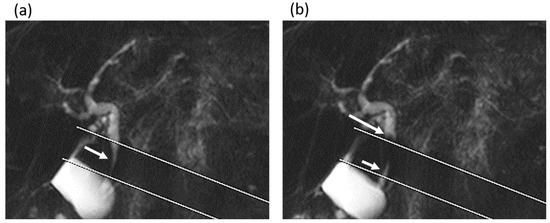

Figure 3.

A 62-year-old man in the gallstone group. (a,b) Cine-dynamic MRCP images with a spatially selective IR pulse. (a) The antegrade bile flow appeared as high signal intensity (arrow) within the area of the IR pulse, showing a grading score of 2. (b) The reverse bile flow was seen as low signal intensity outside the area of the IR pulse (long arrow) and was also seen as high signal intensity coming from duodenal papilla side into the area of the IR pulse (short arrow). The grading score of reverse bile flow was classified as 1.

In comparing MRI measurements between the gallstone group and the non-gallstone group (Table 1), the diameter of the common bile duct was significantly larger in the gallstone group (7 (range, 6–8) mm) than in the non-gallstone group (6 (range, 5–7.5) mm) (p = 0.015). The frequency and mean secretion grade of the antegrade bile flow were significantly higher in the gallstone group than in the non-gallstone group (frequency, 8 times (range, 4–11) vs. 3 times (range, 0–8); mean secretion grade, 0.55 (range, 0.25–0.85) vs. 0.2 (range, 0–0.4)), while no significant differences in those values of the reverse bile flow were found between the groups (frequency, p = 0.729; mean secretion grade, p = 0.703) (Figure 3 and Figure 4).